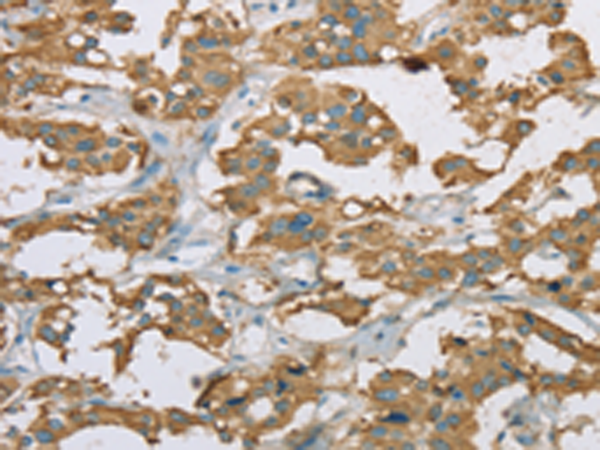

分类: 科研抗体货号: P08269别名: CRI1; EID-1; RBP21; PTD014; C15orf3; PNAS-22; IRO45620应用: IHC反应种属: Human